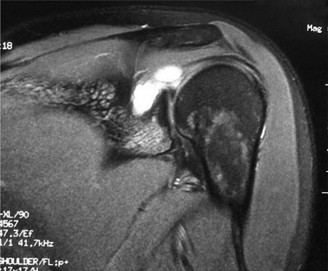

A 45-year-old carpenter presents with shoulder pain that has been ongoing for the last 3 months. He denies any significant injury. He describes night pain and significant discomfort at work. His imaging is shown in Figure 2–9. What is the most likely diagnosis?

Figure 2–9_From Shi LL, Mullen MG, Freehill MT, et al. Accuracy of Long Head of the Biceps Subluxation as a Predictor for Subscapularis Tears. _Arthroscopy 2015;32(4):615–619.

Discussion

The correct answer is (A). Medial subluxation of the biceps tendon as seen in this MRI is commonly associated with a tear of the subscapularis tendon which attaches to the lesser tuberosity. This patient’s pain may in part be attributable to the subscapular tear and this should be evaluated for during physical examination. Supraspinatus tears (Answer B) cannot be easily visualized on axial views and are not associated with medial biceps subluxations. A labral tear and ALPSA lesion (Answers C and D) are not seen on the images provided. The question stem and MRI are not suggestive of shoulder instability (Answer E). Objectives: Did you learn...? Diagnose and treat acute rotator cuff tears?